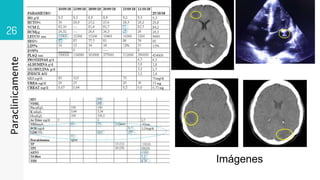

26

Paraclinicamente

Imágenes

12/09/18

▹ 12/09/18

11/10/18

• #83 12 09 18 Area hipodensa en sustancia blaca subcotical en región frontal 20x17 mm 23-32 ud Onfl con dedema perilesional 11 10 18 imagen hipodensa digitiforme en rango 42- 47 Unid Onfil cortico-subcortical en lóbulo frontal derecho, 17.25 und Onfil lóbulo parietan e imagen en región occipital sin aumento de la amplitud de los ventrículos RM 30 10 18 se observan imágenes algunas hipodensas en secuencias T1, otras de señal intermedia muy heterogéneas, hipointensas en secuencias Flair y T2 con realce importante algunas en forma nodular, otras en forma periférica posterior a la administración de gadolinio, las de la región temporal derecha y occipital ipsilateral, con edema perilesional, mucho más importante en la de la región occipital, que debe correlacionarse con antecedente clínico reciente. En el Centro semioval en el lado izquierdo se observan pequeñas imágenes puntiformes hiperintensas en secuencias Flair y T2 pueden corresponder a lesiones vasculares isquémicas de pequeños vasos